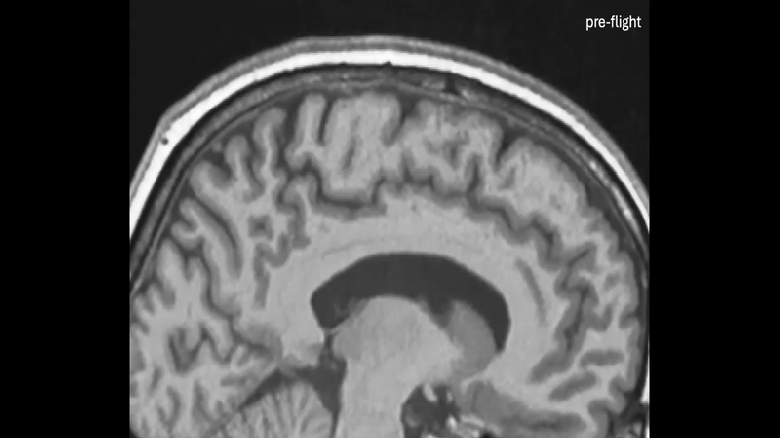

Авторы работы проанализировали данные МРТ 26 астронавтов, сделанные до и после их миссий на МКС. Результаты сравнили с данными 24 добровольцев, участвовавших в эксперименте с длительным (60 дней) пребыванием в положении с наклоном головы вниз на 6 градусов, имитирующем воздействие невесомости на распределение жидкостей в организме.

Учёные обнаружили существенные различия между мозгом астронавтов и добровольцев. У астронавтов мозг смещался вверх сильнее, и эти изменения становились более выраженными с увеличением продолжительности пребывания в космосе. Так, у астронавтов, находившихся на МКС в течение года, моторная кора (участвующая в контроле движений) сместилась вверх примерно на 2,5 миллиметра.